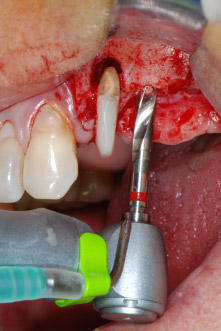

Въпреки това, ние се придържахме към първоначалния си план да запазим и двата зъба като абатмънти за временен мост по време на 6-месечната остеоинтеграция на имплантите. При повторна интервенция, ситуацията трябва да се преразгледа. Първо, в опит да се овладее ендо-перио проблема, останалата повърхност на зъба е внимателно обработена с пиезохирургично оборудване (Piezomed, W&H, използван с накрайник S1 под формата на шпатула, първоначално проектиран за ерозия на латералната синусна стена) (Фиг. 4).